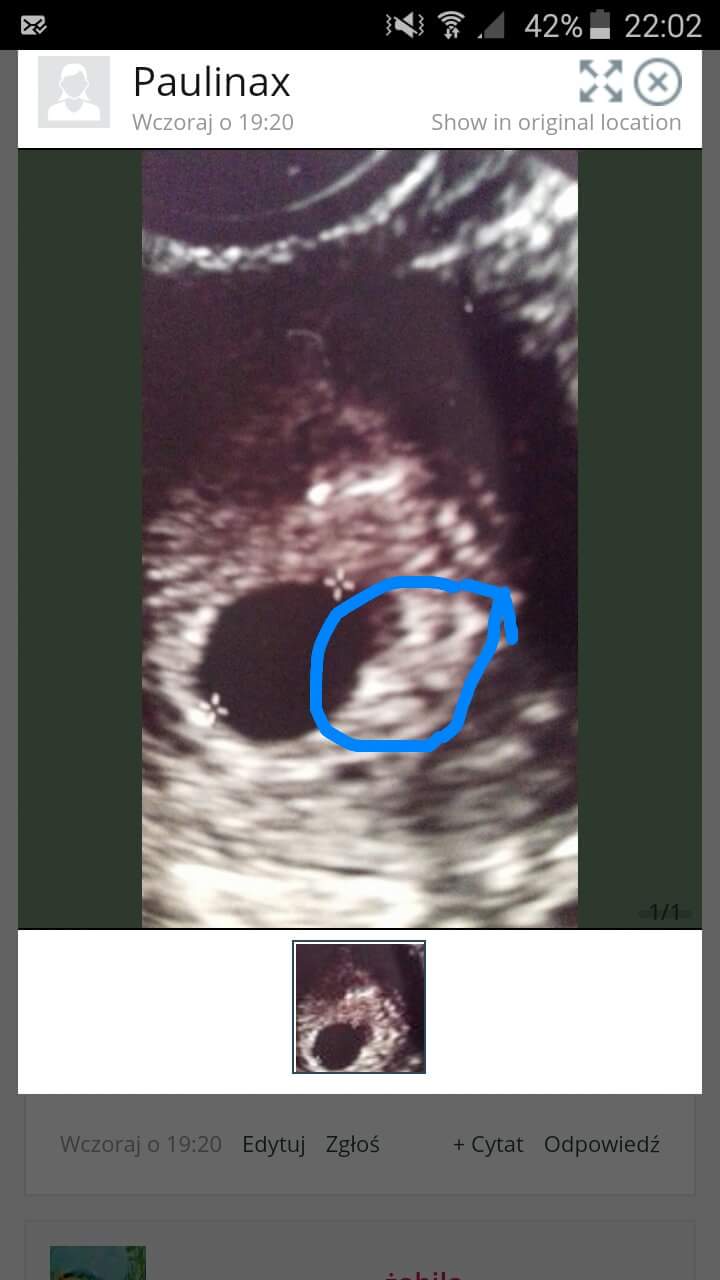

Powiedzcie mi czy tutaj coś więcej widać niż pęcherzyk?

Wcześniej nie miałam nic w środku pecherzyka.

Nie znam się dlatego pytam